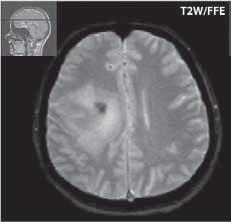

Základním cílem zobrazovacích metod je vyloučení ostatních, nenádorových, někdy expanzivních procesů (abscesu, vstřebávajícího se hematomu, různých typů cyst…), která mají zpravidla jiné klinické vedení. Při zobrazení nádorů bychom se měli snažit zodpovědět tři základní otázky, charakterizující tumor:

1. typing – odlišení nenádorových patologických procesů a snaha o histologickou klasifikaci tumoru.

2. staging – hodnotí stupeň pokročilosti růstu nádoru, kde kromě radiologického nálezu je nutné vzít v úvahu i neurologické a histologické vyšetření.

3. grading – určení stupně vyzrálosti nádoru, stupeň malignity (četnost mitóz, jaderná atypie, angiogeneze, nekrózy).

Základní rozdělení nádorů je intraaxiální (vycházející z mozkové tkáně), např. astrocytom, oligodendrogliom, ependymom…a nádory extraaxiální mající původ v tkáních okolních – např. meningeom, adenom hypofýzy… Dalším možným členěním je na nádory primární a sekundární, resp. mozkové metastázy nebo tumory supratentoriální a infratentoriální. Rozlišení na nádory maligní a benigní nemá vždy ostrou hranici, a proto histologové určují stupně malignity I.–IV. (WHO 2007).

Vzhledem k pokrokům v diagnostickém zobrazování se daří zlepšovat substrátovou diagnostiku. Například u gliomů nedávné práce ukázaly, že nález na ADC mapě může pomoci při odlišení nádorů s vyšším stupněm malignity, je zde nižší hodnota než u gliomů s nižším stupněm malignity (u maligních je vyšší buněčnost, tedy pokles difuzivity). Jiné práce se zabývaly perfuzí a ukázaly, že k odlišení pomáhá rCBV (zvýšené u vyššího gradingu tumorů), především na odlišení II. a IV. či III. a IV. stupně. Jako nejvýtěžnější se jeví pro jejich diferenciaci užití kombinace ADC mapy s rCBV.